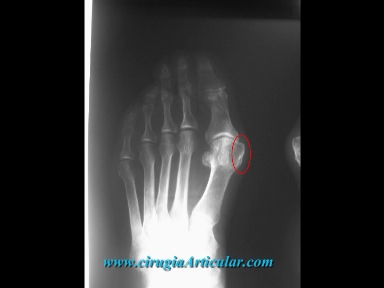

Foto 2

En la radiografia se puede apreciar el crecimiento de hueso excesivo que se produce en el borde interno del pie.